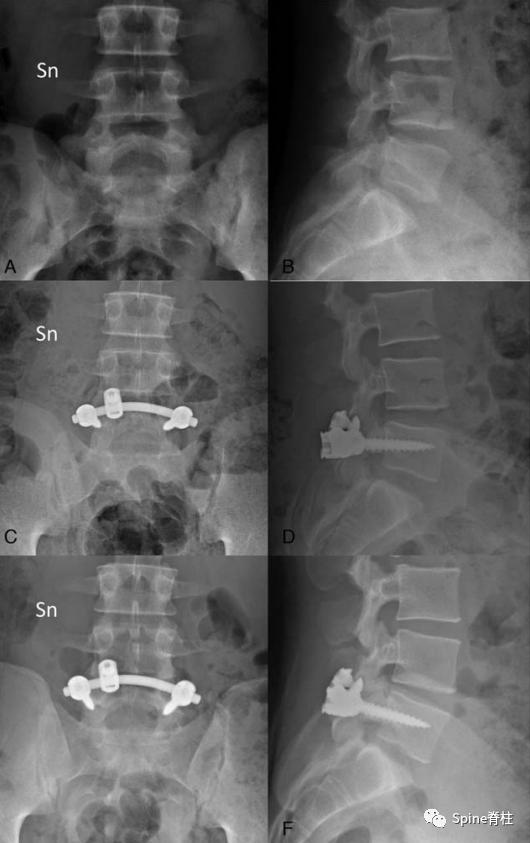

2019年国内解放军总医院第七医学中心李放教授团队。根据临床特点和影像学表现将所有病例分为3型:

- A型为单纯型峡部裂,无椎间盘突出及腰椎滑脱;

- B型为峡部裂伴有轻度椎间盘突出或I度滑脱,无神经压迫症状及体征;

- C型为峡部裂合并I度或Ⅱ度滑脱并椎间盘突出同时有神经压迫症状及体征。

并建议保守治疗无效的青年战士A、B型腰椎峡部裂病例采用椎弓根螺钉固定,峡部自体髂骨原位植骨融合率高,效果好,C型战士峡部裂则宜采用后路椎间植骨融合椎弓根螺钉内固定术。

左图:13岁腰椎双侧峡部裂(进展期)

右图:经上述腰围治疗3个月复查CT可见断裂的峡部达到骨愈合

一项采用支具固定、限制活动进行保守治疗的前瞻性研究发现:

- 峡部裂早期的融合率为94%,融合时间平均为3.2月;

- 进展期伴椎弓根水肿的融合率为64%,融合时间为5.4月;

- 进展期不伴椎弓根水肿的融合率为27%,融合时间为5.7月;

- 终末期峡部裂融合率为0。